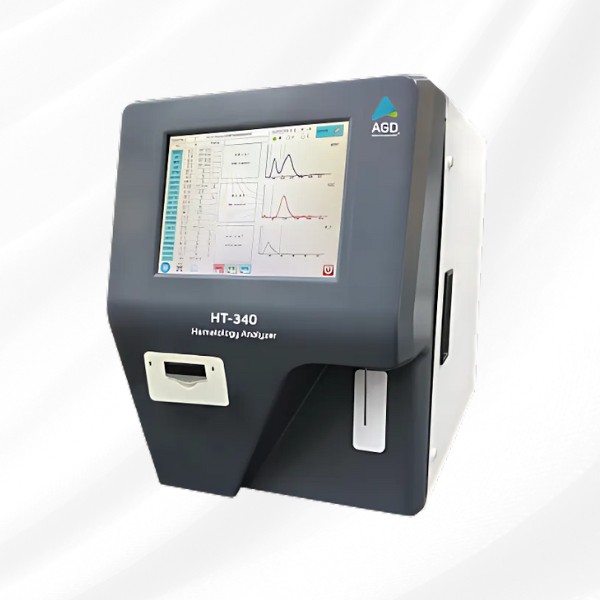

Advanced CBC analyzer with 3/5-part differential and user-friendly interface.